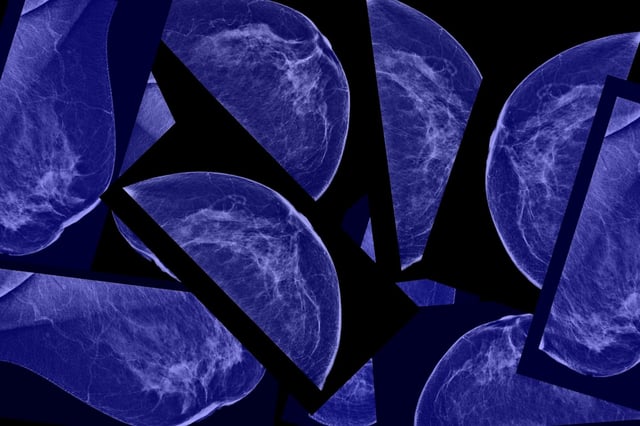

Push to Expand Early Cancer Screening Highlights Age-40 Mammograms and HPV Self‑Sampling

• U.S. guidance cited by a Mayo Clinic oncologist recommends beginning breast screening at 40, with annual mammograms and supplemental imaging for very high risk or extremely dense breasts decided through shared discussions with clinicians.